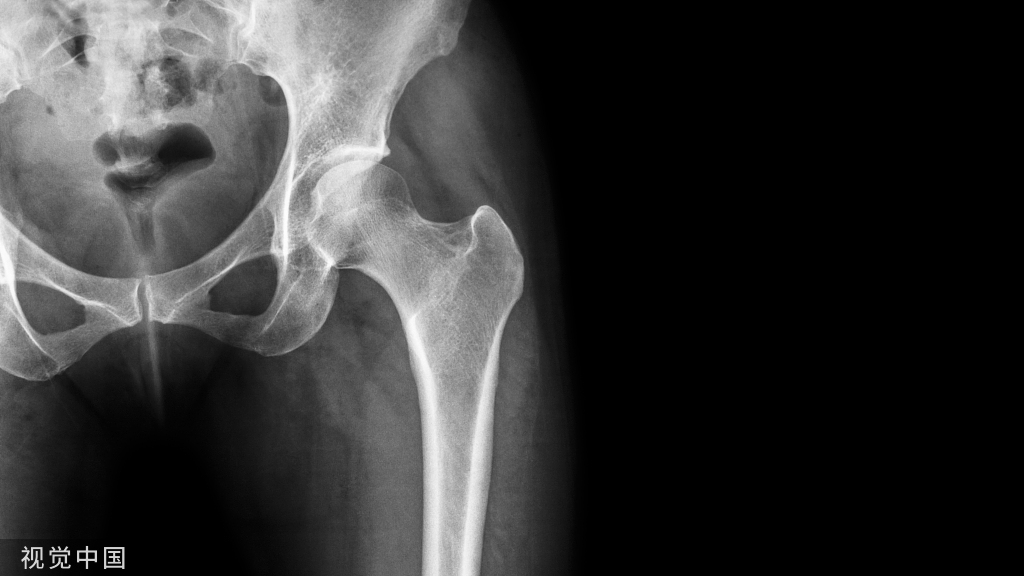

(1)股骨髁上骨牵引

适用于有移位的股骨骨折、骨盆环骨折、髋关节中心脱位等。也用于陈旧性髋关节脱位或先天性髋关节脱位的术前准备、由于软组织挛缩引起的髋关节畸形,以及用皮肤牵引无效者。

髌骨上缘,作一条与股骨垂直的横线,再沿腓骨小头前缘及股骨内髁隆起最高点,各作一条与髌骨上缘横线相交的垂直线,交点即为针进出点的标记。消毒、局麻后,将皮肤稍上提,由大腿内侧标记点刺人斯氏针直至股骨。注意保护大收肌裂孔附近的股动、静脉及其分支和隐神经,保持针水平位,与股骨垂直,使其由大腿外侧标记点穿出,并使两侧牵引针外露部分等长。

安装牵引弓后进行牵引,同时床脚抬高20cm左右,作对抗牵引。牵引的重量应根据病人的体重及伤情决定,一般为体重的1/7~1/10。